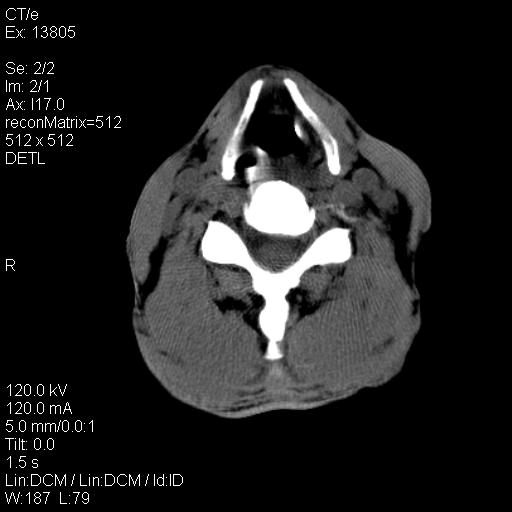

上腹部疼痛一月,呕吐10天,发现左侧颈部包快10天 胸部cr片未见明显异常。

考虑淋巴瘤可能性大,不排除转移瘤。

腹膜后淋巴结增大,转移、淋巴瘤?胰腺增大,胰腺炎?占位?颈部考虑增大淋巴结。建议腹部增强扫描。

左侧胸锁乳突肌下方、颈血管旁低密度肿块影,肿块密度尚均匀,边缘大部分清楚,邻近组织稍受压移位。考虑颈部神经鞘瘤可能性大。